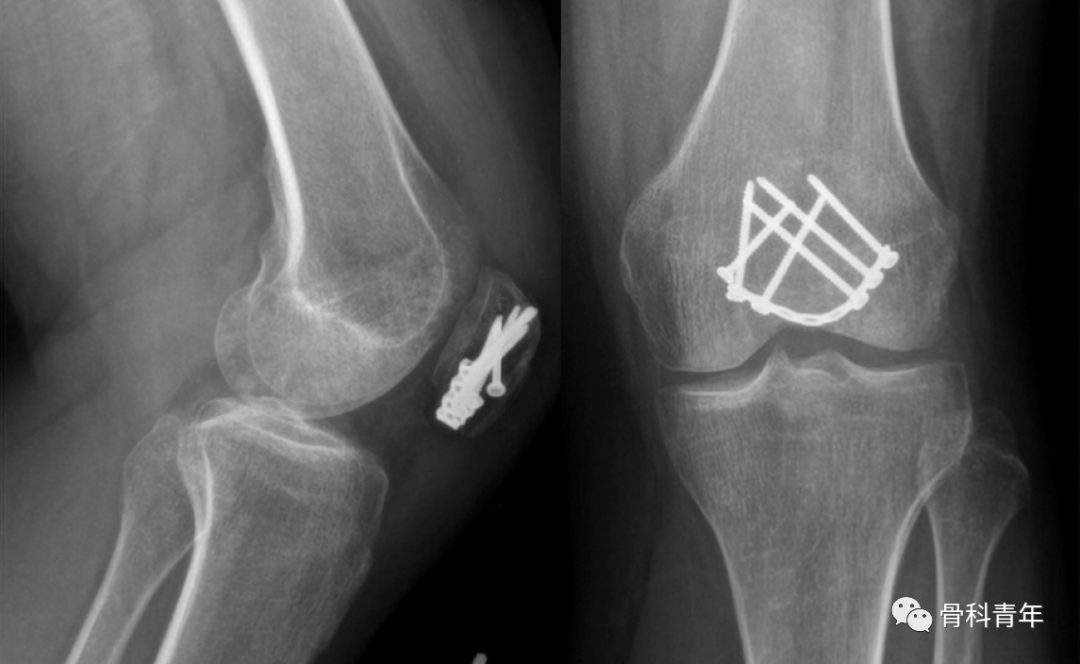

髌骨下级粉碎骨折蓝式钢板固定

3.钢板固定

钢板固定已经成为一种新技术来解决张力带钢丝的缺点。Moore等回顾了36例C2和C3髌骨骨折患者采用前路固定角度钢板治疗的病例,他们发现有17名需要螺钉辅助固定,2名患者需辅助钢丝环扎。

Lorich等描述了9名患者,他们通过外侧关节切开术和使用允许多平面螺钉固定的新型笼形钢板进行复位。所有患者在平均23周达到愈合。只有1名患者出现需要移除的有症状植入物。未发现骨坏死、感染或伤口并发症的病例。由同一作者进行的一项前瞻性队列研究比较了25例接受相似多平面笼式固定的患者和33例接受张力带固定的患者。他们注意到,在钢板组中,大腿肌肉萎缩和膝前方疼痛明显减少。

钢板植入物通常有多个螺钉孔和锁定螺钉选项,这可能使它们更适合于粉碎骨折的固定。此外,低切迹和/或预成形以匹配髌骨独特解剖结构的设计可减少植入物突出和随后的植入物移除需要。

总之,髌骨骨折钢板固定似乎是一种有前途的技术,可治疗具有挑战性的骨折类型。